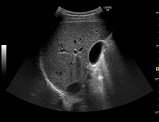

団塊の世代が75歳以上となる、いわゆる「2025年問題」を前に、医療サービス提供のあり方に変革が求められてきている。その中で、超音波検査は精度の向上と診断の効率化に貢献することから、その活用に期待が高まっている。超音波検査は体への負担が少なく、リアルタイムの画像化によるさまざまな領域の検査が可能であるが、一般的にCTやMRIと比べ視野深度が限られ、体格によっては深部まで超音波が届きづらいことや浅い部分(表在)の抽出が困難であることが課題とされてきた。また、動くことが難しい高齢の患者にとっては診断装置のある検査室まで行くことが難しい場合もあり、軽くて検査室外への持ち運びがしやすく、質の高い検査を可能とする超音波診断装置の開発が求められてきた。 この度発売される「LOGIQ S8 with XDclear」と「LOGIQ E9 with XDclear2.0」は、日野本社で開発された高感度プローブ「XDclearプローブ」の搭載により、体の浅部から深部にいたるまで超音波を届けることが可能になった。腹部一般用の「C1-6-Dプローブ」は、深部の観察範囲を広げることで、体格による画像抽出困難を軽減し、形状が小さいマイクロコンベックスタイプの浅部用「C3-10-Dプローブ」は、血管、小児、腹部など全身のさまざまな部位にあてやすく、表在部の画像の多重エコーなどを解決。

腹部一般用の「C1-6-Dプローブ」と浅部用の「C3-10-Dプローブ」の搭載により、浅部や深部の画質向上を実現。一台で多様な質の高い検査を可能とする。

同社では、GEヘルスケアの中核開発・製造拠点として、これまで30年以上にわたり世界の医療現場に日本発の先進プローブを届けてきた開発・製造チームの密な連携のもと、プローブの素材を見直し、従来のセラミックに替えて、電気信号と音の変換効率に優れたシングルクリスタル(高密度単結晶)を採用し、これまで使用されていなかった音響エネルギーを有効活用するアコースティックアンプリファイヤー技術、ならびにレンズ表面での温度上昇を抑えてプローブが最大限の性能を発揮できるようにするクールスタック技術を搭載することで、この課題を克服。画質と診断深度の両立を可能にするXDclearプローブの開発で、皮膚に近い表在部から体内深部まで広範囲にわたって均一な高精細画像の描出を可能とした。